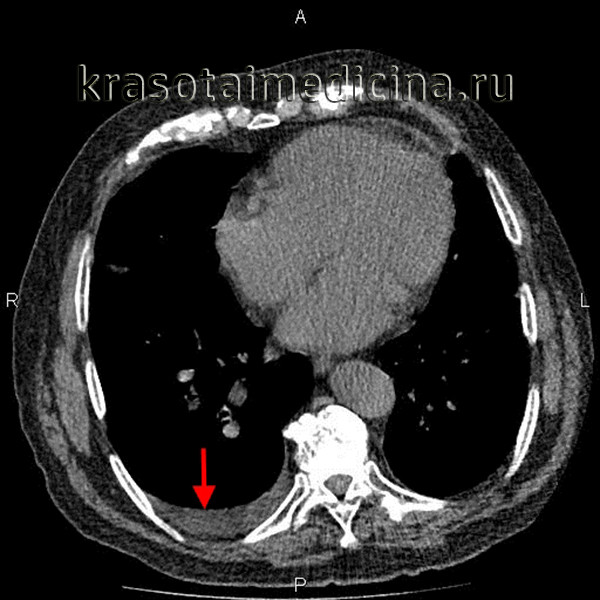

- Рентген. Полипозиционная рентгенография и рентгеноскопия легких при эмпиеме плевры обнаруживают интенсивное затенение. Для уточнения размеров, формы осумкованной эмпиемы плевры, наличия свищей выполняют плеврографию с введением водорастворимого контраста в плевральную полость. Для исключения деструктивных процессов в легких показано проведение КТ, МРТ легких.

- Сонография. В диагностике ограниченных эмпием плевры велика информативность УЗИ плевральной полости, которое позволяет обнаружить даже небольшое количество экссудата, определить место выполнения плевральной пункции.

Для первичного выявления осумкованного плеврита чрезвычайно важны данные полипозиционой рентгенографии грудной клетки (в прямой, боковых и косых проекциях) и рентгеноскопии легких. Рентгенологически осумкование проявляется в виде затемнения характерной локализации и формы. В сложных случаях для дифференциальной диагностики требуется наложении искусственного пневмоторакса и пневмоперитонеума, проведение КТ легких. Длительное существование осумкованного плеврита может отразиться на состоянии легочной паренхимы. Поэтому для оценки изменений прилежащих отделов легкого (бронхов, сосудов) используются рентгеноконтрастные исследования - бронхография и ангиопульмонография.